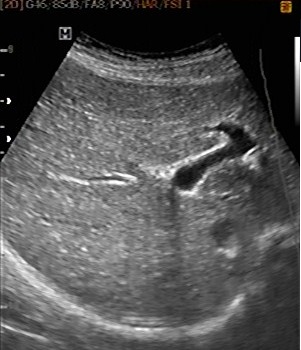

Coupe transverse

recurrent -Bifurcation portale : A travers du

foie , la bifurcation de la veine porte |

recurrent "Tete de Mickey " a travers du foie , le

tronc

de la vein porte . Artere hepatique , le canal choledoque et la

vesicule biliaire peut en vue totalement sủr cette

coupe |